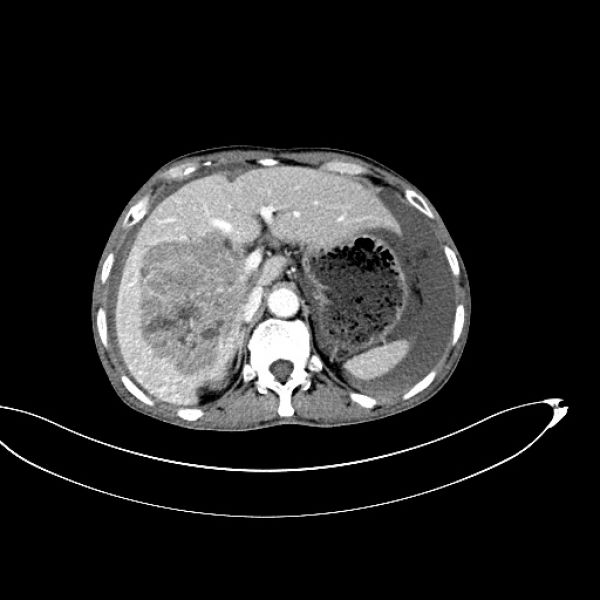

术后复查CT